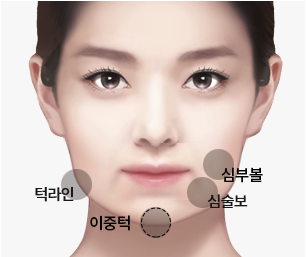

BUCCAL FAT REMOVAL

심부볼지방제거

심부볼지방제거는 볼 안쪽 깊숙이 위치한 지방 덩어리를 제거하여

둥글고 통통한 얼굴을 갸름하고 세련된 V라인으로 만드는 수술입니다.

웃을 때 불룩한 볼,

갸름한 V라인으로 개선합니다

불룩한 볼

웃을 때 볼이 불룩하게 튀어나와통통한 얼굴

심부볼 지방이 많아사각턱 강조

볼 지방으로 인해V라인 원하는 경우

갸름하고 세련된어려 보이는 인상

볼 지방 때문에다이어트 후에도 볼살

심부볼의 위치

심부볼 크기

심부볼의 크기와 위치를얼굴 골격

광대뼈, 턱선 등피하지방량

볼의 피하지방 양을 측정하여피부 탄력도

피부 탄력을 평가하여나이

연령대를 고려하여얼굴 전체 비율

이마, 코, 턱과의 조화를